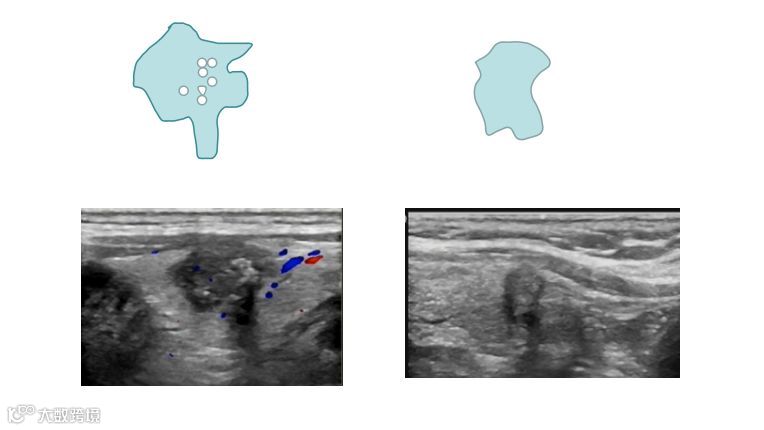

怎么判断结节的良性和恶性??

“以貌取结”&FNA(细针抽吸活检)

良性结节图

恶性结节图